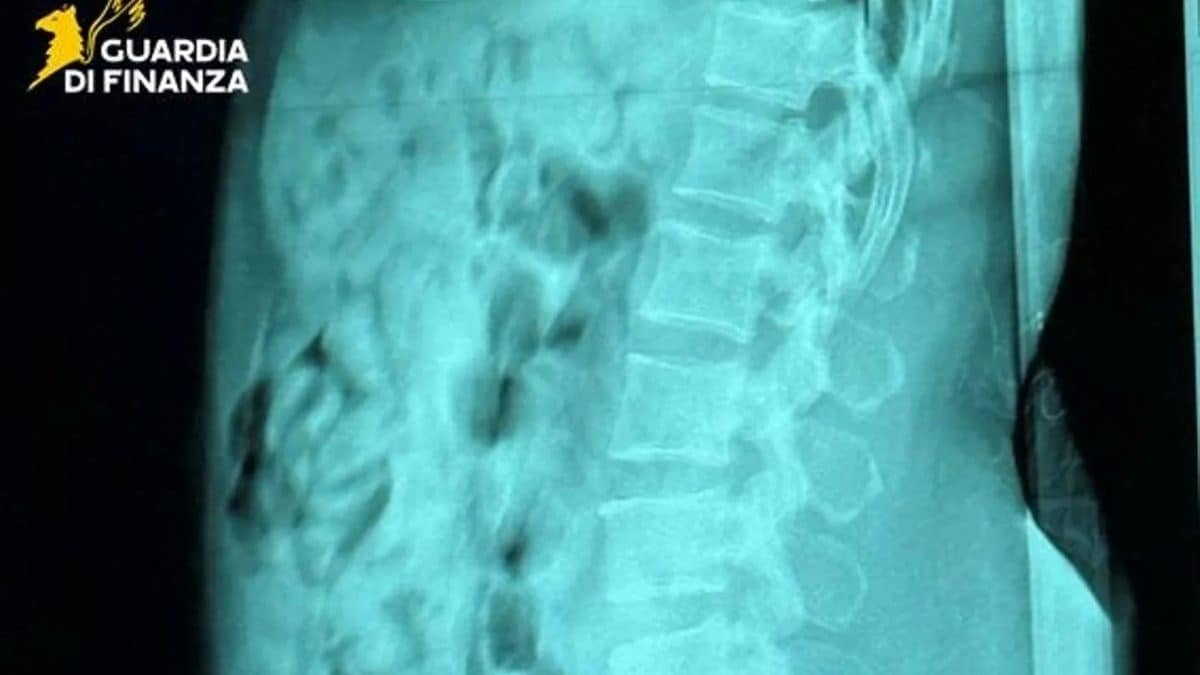

Una 46enne è stata arrestata in flagranza di reato perché trasportava nello stomaco 120 ovuli di eroina. La donna è stata intercettata dai funzionari dell'Agenzia delle Dogane e Monopoli (Adm) e i militari della guardia di finanza all'aeroporto Orio al Serio di Bergamo dopo che era appena atterrata con un volo da Bruxelles, in Belgio. Gli esami radiologici svolti all'ospedale Papa Giovanni XXIII di Bergamo hanno confermato la presenza dei contenitori plastici al cui interno erano stati inseriti 1.393 grammi di eroina. La 46enne è stata, infine, condotta nel carcere bergamasco a disposizione dell'autorità giudiziaria.

Così, agli addetti alla dogana italiana e i militari della guardia di finanza avrebbe ammesso che stava trasportando sostanza stupefacente attraverso la tecnica degli ovuli, in gergo body packer. La 46enne è stata, quindi, accompagnata all'ospedale Papa Giovanni XXIII di Bergamo dove è stata sottoposta a esami radiologici che hanno confermato la presenza di 120 contenitori plastici avvolti in strati di nastro adesivo nel suo stomaco. Una volta terminata l’espulsione degli involucri, il quasi chilo e mezzo di eroina è stato sequestrato e la 46enne condotta nel carcere di Bergamo.